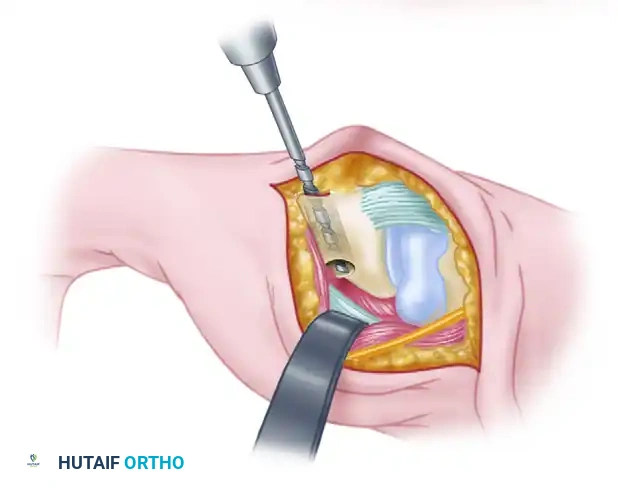

Figure: Gouge tract created in the sagittal diameter of the metacarpal, emerging at its volar beak. A small branch of the radial nerve is retracted volarly.

Intraoperative view demonstrating the creation of the metacarpal tunnel.